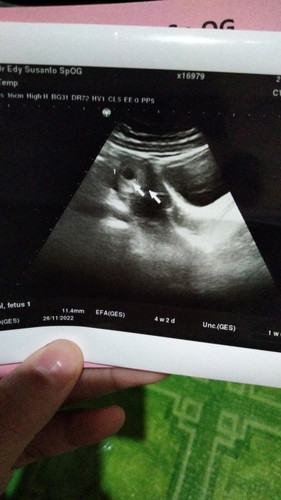

Bunn saya mau tanya nih. HPHT saya tgl 23 januari 2022. Trus bulan februari saya test dan hasilnya positif garis 2. Tgl 11 bulan maret kemarin saya pergi ke usg 2D , tp kata bidannya belum terlihat padahal usianya sudah 6 mingguan. Itu kenapa ya bunn. Mohon dijawab ya🙏🙏 #pleasehelp #bantudijawabbunda #ingintahu #seriusnanya #bantusharing #seputarankehamilan #mkshbun